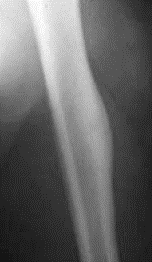

2

Q

Pathology?

A

Osteomalacia

overabundance of organic matrix that is not mineralized, due to a deficiency of vitamin D; see widening of osteoid seams